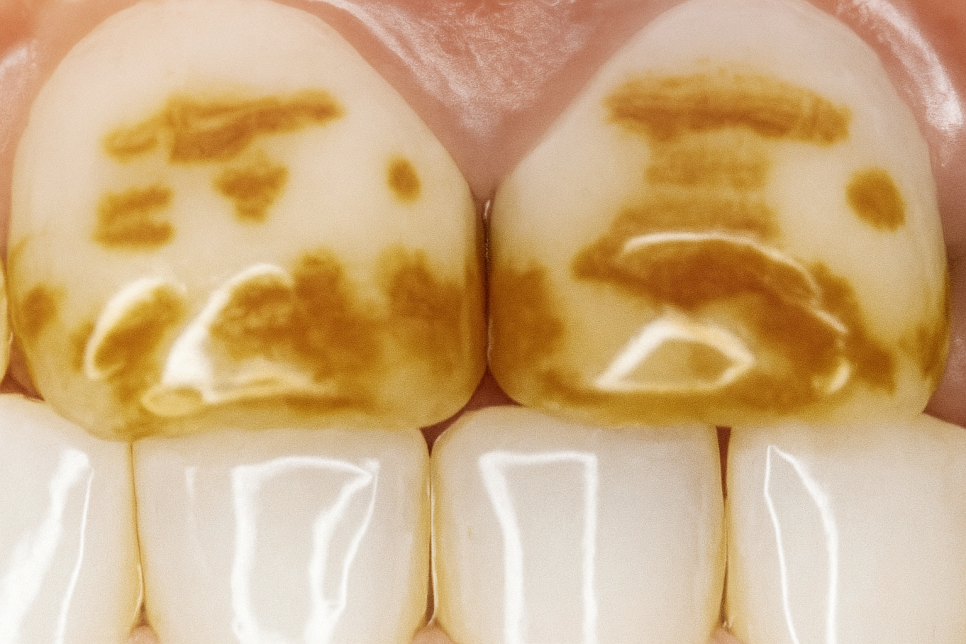

완성된 라미네이트의 적합도를

확인하고 임시 부착을 통해

이에 잘 맞는지 체크합니다.

25.07.14

부착을 완료하고 교합과 심미성을

점검하여 치료를 완료할 수 있습니다.